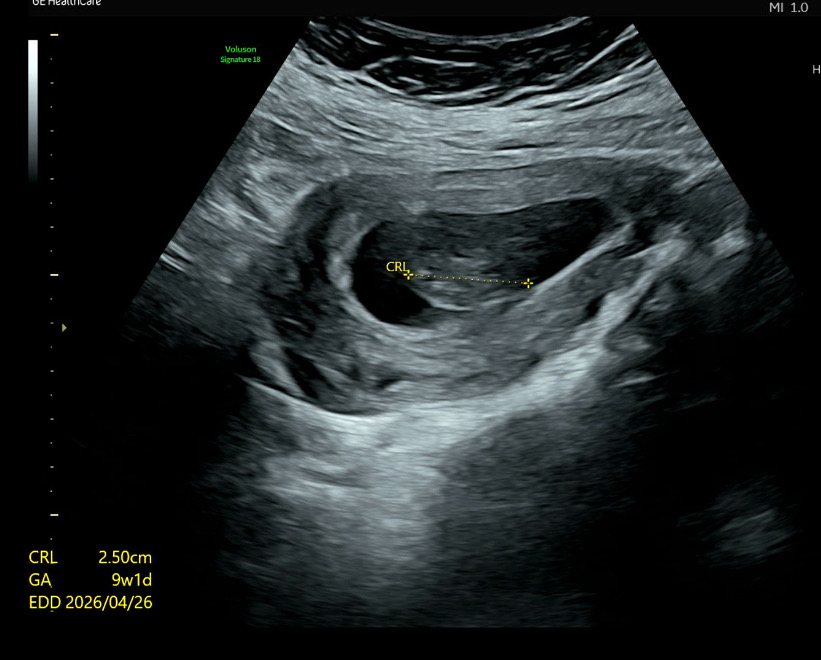

9주 초음파가 너무 흐릿해요

지금 다니는 병원에서 찍은 초음파가 너무 흐릿해요 이 주변에선 꽤 큰 분만 병원인데도요 2.5cm고 이 주수면 다른 분들처럼 젤리곰이 보여야 할 거 같은데 너무 흐릿하죠? 선생님은 보시면서 여기가 머리고 여기가 몸이예요 하는데 음? 뭘 보고 그러시는건지 제 눈엔 하나도 안 보이더라구요 추석연휴땜에 이제 3주 뒤에나 가는데 다른 병원에 가서 한번 초음파만 볼까도 싶네요 주변에 있는 아무 산부인과 가도 초음파 봐줄까요?